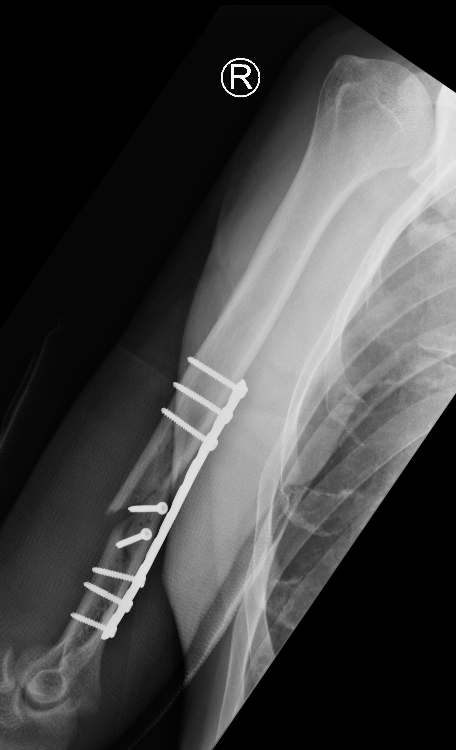

Management Nonunion Humerus Fractures

Management

- systematic review of union rate after operative intervention of humeral shaft non union

- plate only 95%

- plate and bone graft 98%

- IMN 66%

- IMN + bone graft 88%

- external fixation 98%

Technique

Approach

- fracture site dependent

- 4.5 mm plate with 6 cortices above and below

- if use 3.5 mm long proximal humeral plate, suggest 8 cortices below

- use iliac crest bone graft

- consider dual plating in proximal fractures with insufficient fixation, or in poor bone quality